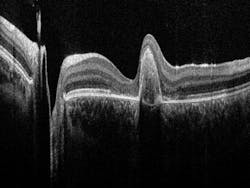

Bioptigen develops and manufactures OCT systems and software, with products for clinical as well as translational research applications. Using low-power, near-infrared (NIR) light, the OCT systems generate high-resolution, volumetric images of the eye. The company currently markets the FDA-cleared and CE-marked Envisu C2300 OCT for handheld, pediatric, and perioperative applications, and sells advanced ophthalmic OCT imaging systems for preclinical research globally.

OCT utilizes interferometry to create cross-sectional views of different types of tissue. This noninvasive technique is used to detect and monitor morphological changes of ocular tissue, particularly retinal layer thickness, which can give insight into pathological conditions such as glaucoma, age-related macular degeneration (AMD), or diabetic retinopathy.